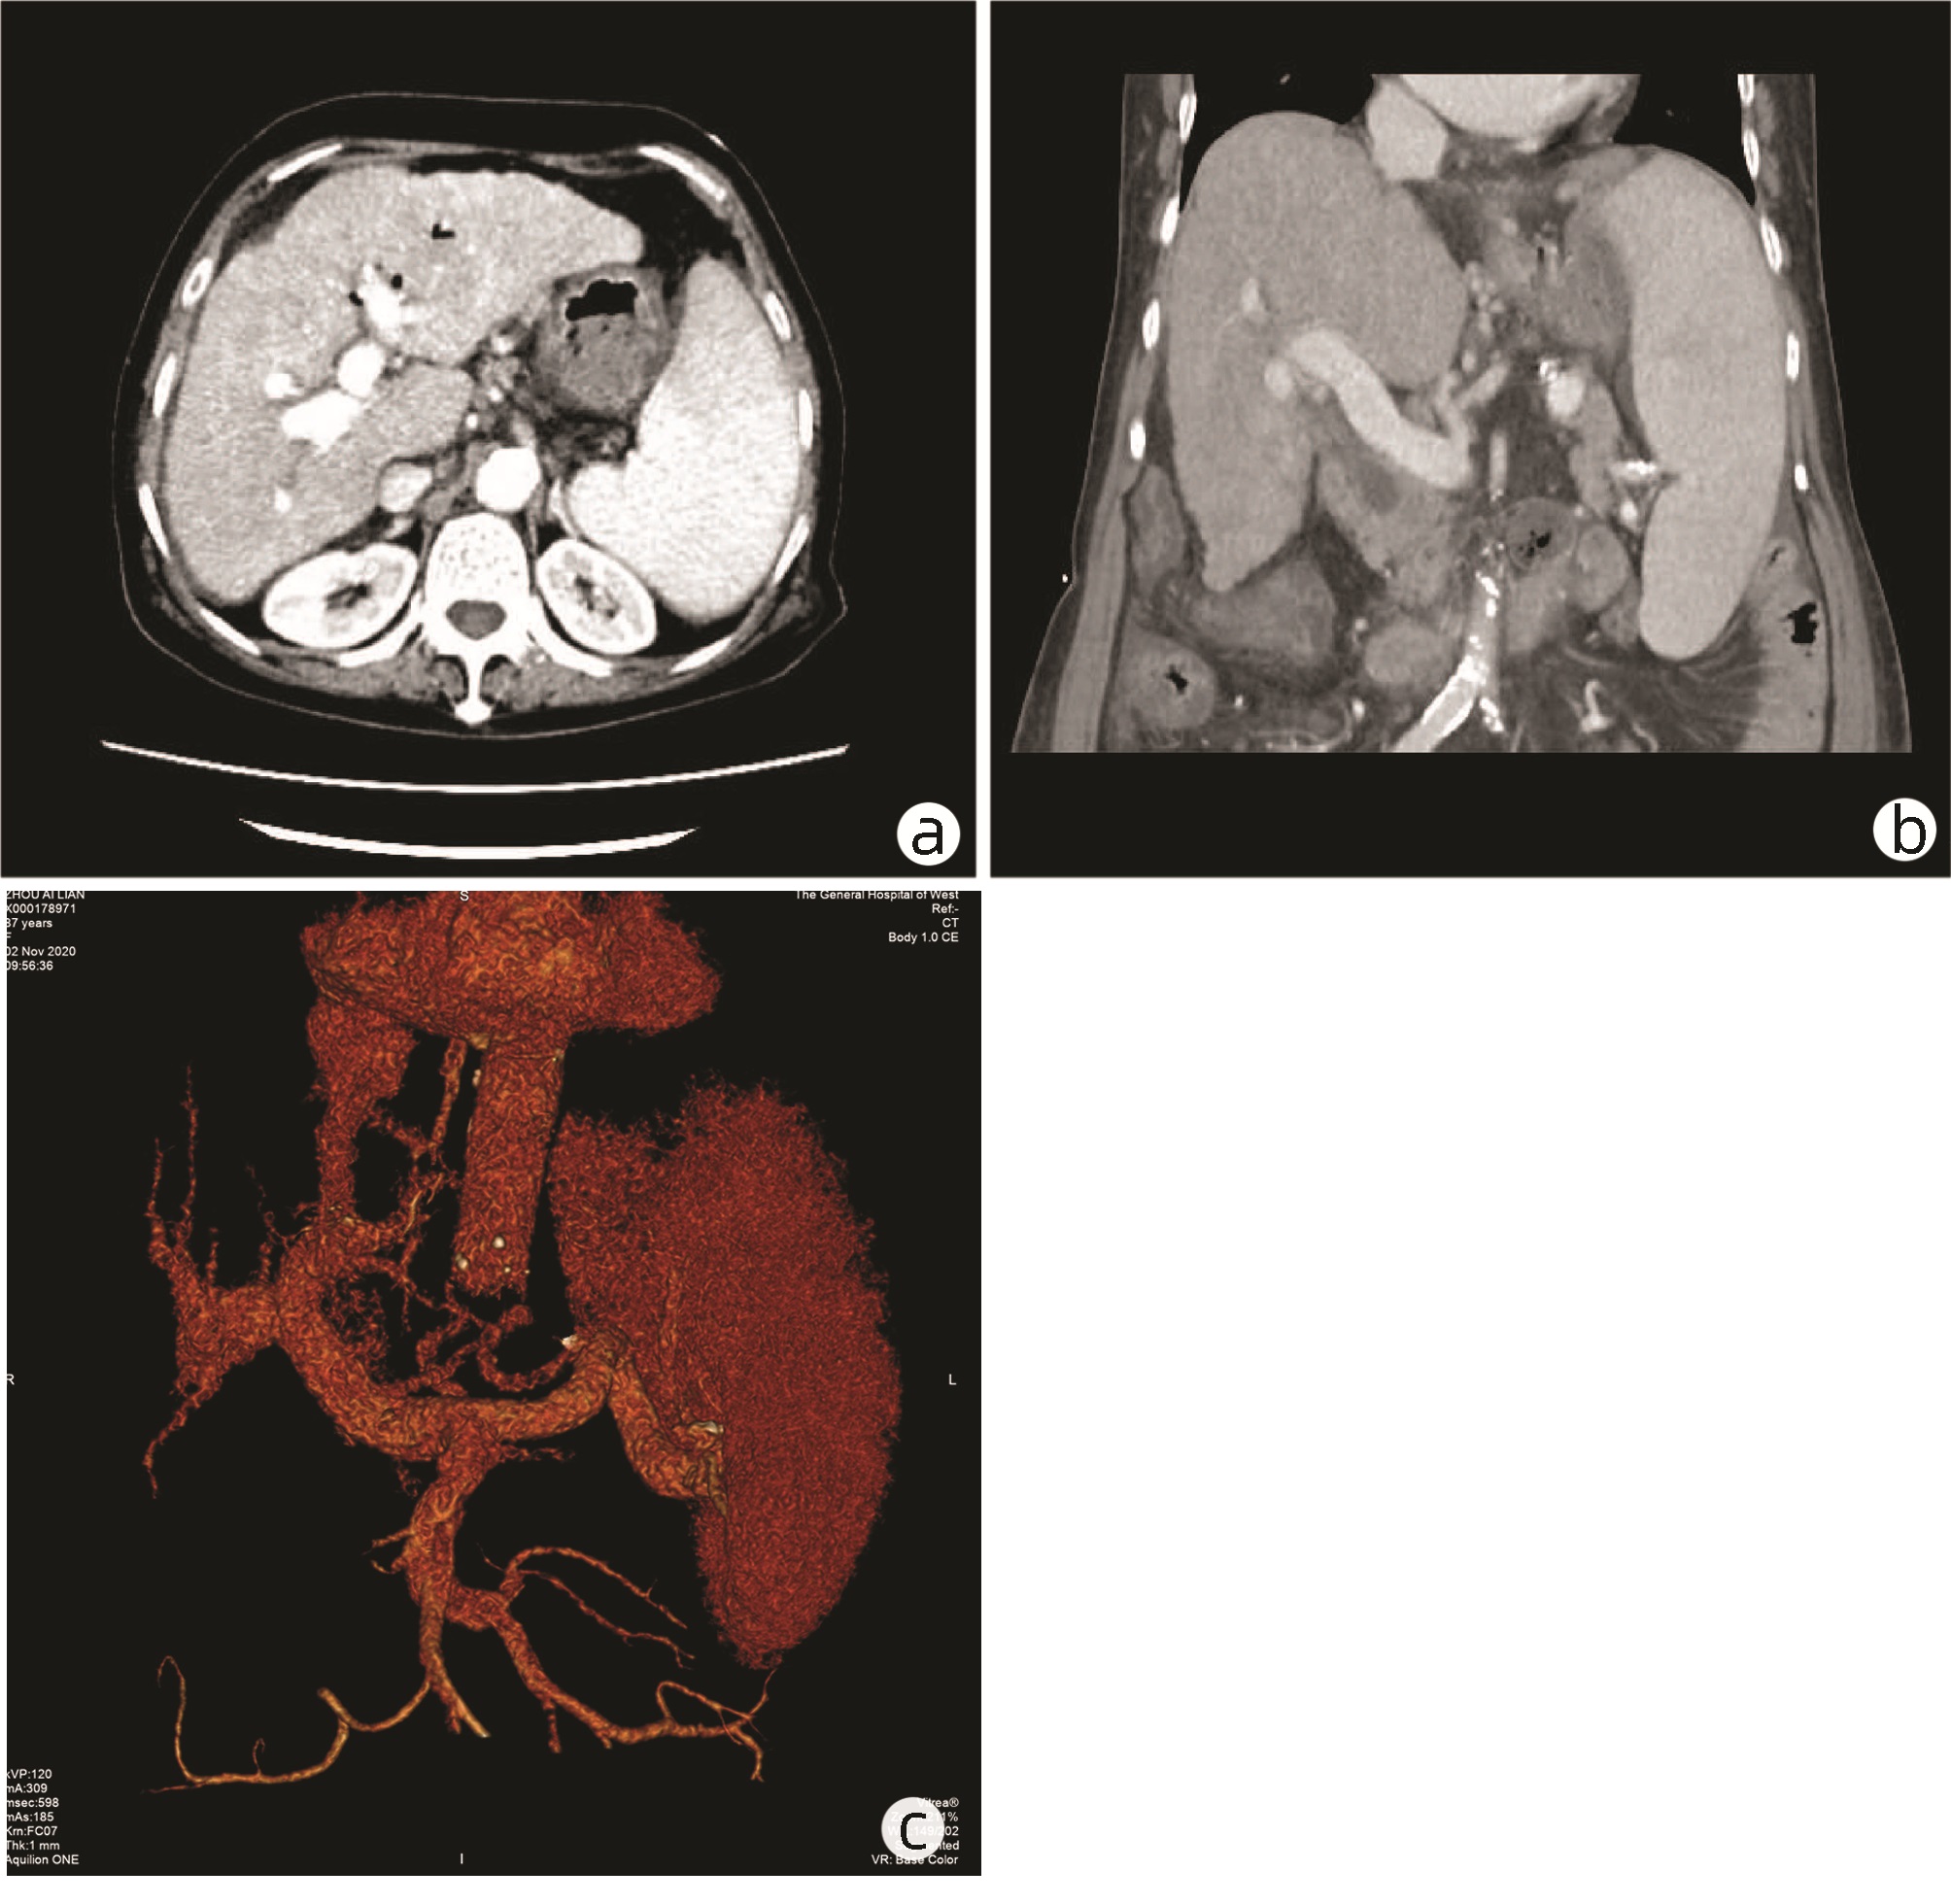

Treatment of unresectable periampullary carcinoma with irreversible electroporation: A case report

Caixia HU, Peng ZHAO, Bojun LIU, Jiasheng ZHENG, Yonghong ZHANG

2022, 38(10): 2344-2345. DOI: 10.3969/j.issn.1001-5256.2022.010.027

Abstract(802) HTML (367) PDF (1924KB)(54)

Abstract: